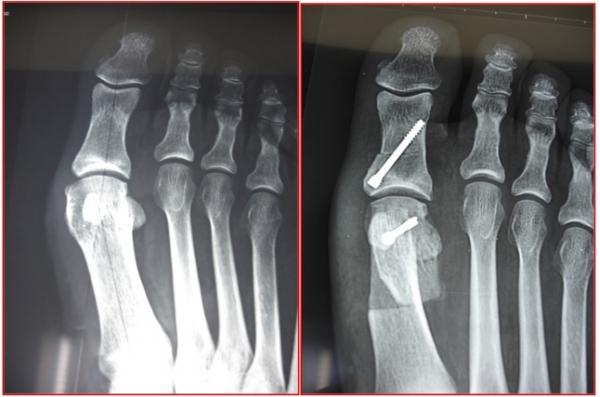

HALLUX VALGUS

Il s’agit d’une déformation qui crée une saillie osseuse sur la partie médiale de l’hallux, à l’origine de phénomènes douloureux et d’une gêne au chaussage. Il s’agit de la déformation la plus fréquente de l’hallux. Elle touche préférentiellement les femmes, parfois dès le plus jeune âge. On ne connaît pas réellement les causes de cette déformation mais l’origine congénitale semble la plus vraisemblable

Radiographie des pieds face et profil en charge +++ avant consultation d’un spécialiste,

Étude de l’architecture global du pied, de l’état articulaire à la recherche d’une arthrose, fracture de contrainte, et mesure des angles.

Chirurgical :

Les techniques « conventionnelles (ciel ouvert) » permettant, sous contrôle de la vue de corriger la déformation.

Au contraire, les techniques « percutanées » utilisent plusieurs incisions millimétriques, permettant le passage d’instruments spécifiques qui sont guidés sous la peau par un contrôle radiographique.